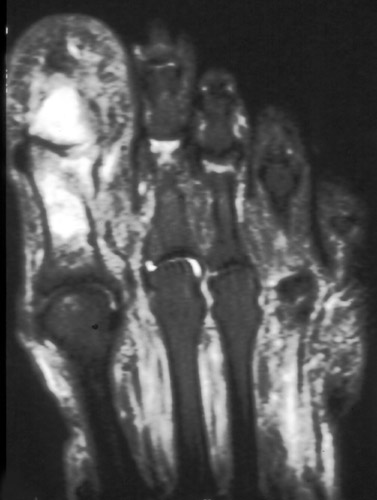

Advanced Imaging of the Diabetic Foot and Its Complications

Imaging of the Diabetic Foot and Its Complications

MRI